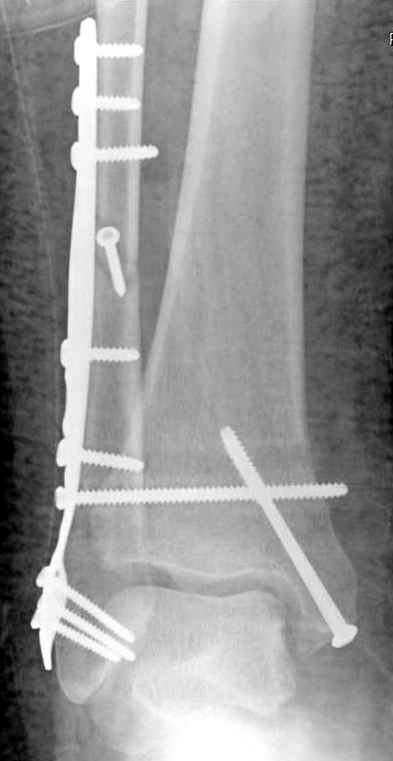

Операция 29 июля

Риторический вопрос - в каком руководстве рекомендован такой способ остеосинтеза наружной лодыжки?

Очевидно, такой результат операции был запрограммирован. При невосстановленной длине и практически нефиксированной малоберцовой кости (этот кортикальный винт - как карандаш в стакане), при неустраненном подвывихе, невправленной и тоже нефиксированной внутренней лодыжке нет стабильной вилки сустава. Если такую операцию сделать даже сразу, а не через 4 месяца, то результат ожидаем

тот же.

Ну а уж если выбран остеосинтез - нначать надо было с репозиции малоберцовой кости с точным восстановлением длины, с фиксацией треть-трубчатой пластиной по задней поверхности. Позиционный винт

избыточен - повреждение практически подсиндесмозное. А если бы

действительно было повреждение синдесмоза - в 4 месяца позиционный винт - не решение. Внутренню лодыжку такую - надо было бы спицами и проволочной петлей. Извините за эти банальности.